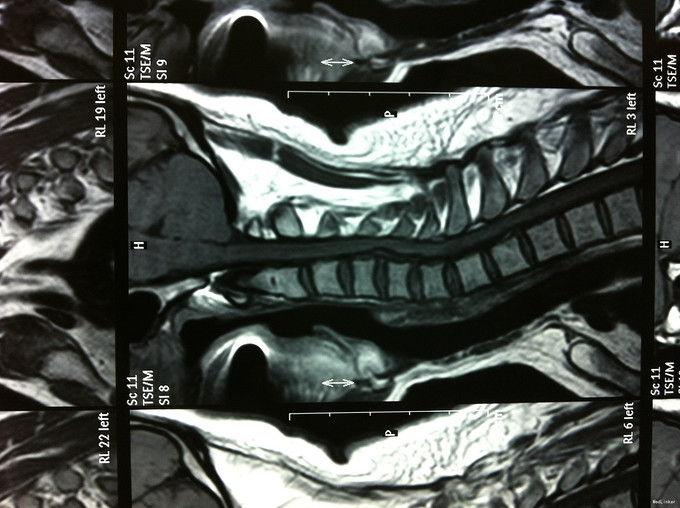

颈肩疼痛1年,加重伴左上肢疼痛、行走不稳1个月 患者1年前无明显诱因出现颈肩部疼痛不适,不伴四肢放射性疼痛、无力,劳累后加重,平卧休息可缓解。1个月前无明显诱因出现颈部疼痛加重,伴左上肢放射性疼痛,行走不稳、双足踩棉感,无高热、寒战,无低热、盗汗。

查体:左侧前臂及手感觉减退,右侧正常,左侧伸腕、伸肘肌肌力4级,右侧伸腕、伸肘肌肌肌力4-5级,双侧霍夫曼综合征阳性,双下肢肌张力高,膝腱反射+++,巴氏征阳性,辅助检查: X-ray:劲椎退行性变 CT及MR:颈椎间盘突出,腰5/6,6/7间盘突出并骨赘形成

诊断:脊髓型颈椎病 处理: 1、完善相关辅助检查,明确诊断,有无手术指证; 2、全麻下行颈椎前路减压,颈椎间盘突出并骨赘形成,行颈6椎体次全切,减压较充分。